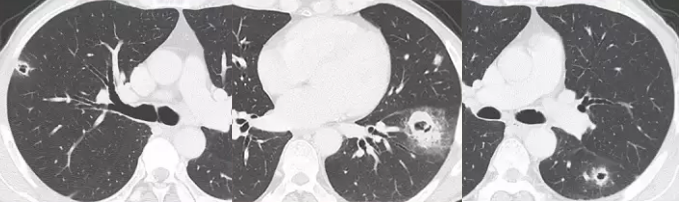

男,63 岁。食管鳞癌术后 3 年,痰中带血丝半年。穿刺证实双肺多发空洞和空泡转移,周围磨玻璃密度是转移瘤引起出血。